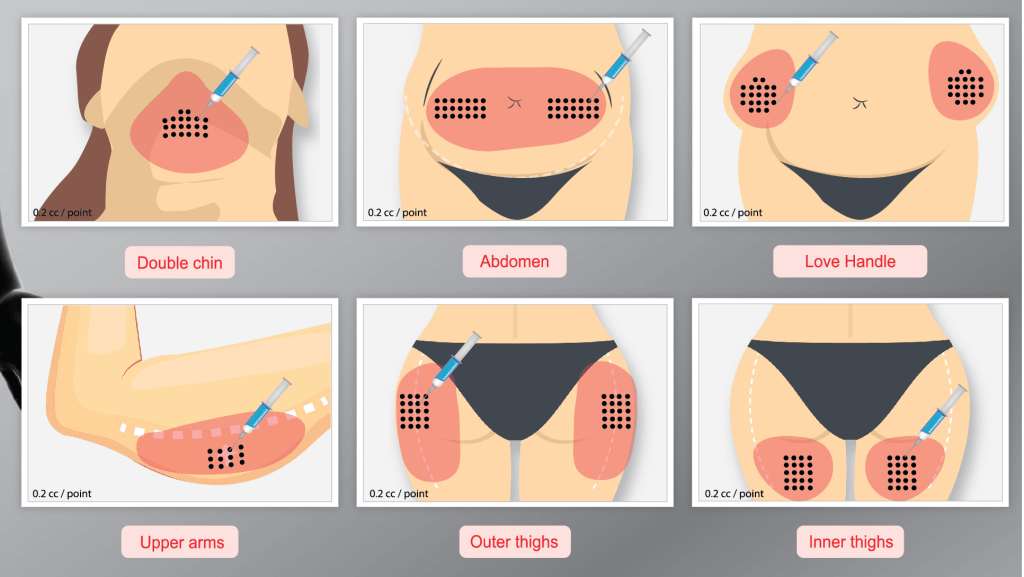

Injektionslipolyse

Fett-weg-Spritze (Injektionslipolyse)

Die Fett-weg-Spritze ist eine minimalinvasive Behandlung zur Reduktion kleiner, störender Fettpolster. Medizinisch heißt sie Injektionslipolyse.

Wie funktioniert sie?

- Es wird ein Wirkstoff (meist Desoxycholsäure oder Phosphatidylcholin) direkt in das Fettgewebe injiziert:

- die Fettzellen werden zerstört

- der Körper baut sie über Wochen ab

- das Fett verschwindet dauerhaft in diesem Bereich

Bekannte Präparate sind z. B. Belkyra (für Doppelkinn).

Geeignete Bereiche:

- Doppelkinn

- Kleine Bauchspeck-Zone

- Love Handles

- Oberarme

- Innenschenkel

- BH-Röllchen

⚠️ Nicht geeignet bei starkem Übergewicht – es ersetzt keine Gewichtsabnahme.

Ablauf & Ergebnisse:

- Dauer: 20–30 Minuten

- 2–4 Sitzungen meist nötig

- Deutliche Schwellung (v. a. am Kinn) für mehrere Tage

- Ergebnis sichtbar nach 4–8 Wochen

Tut es weh?

- Brennen oder Druckgefühl während der Behandlung

- Deutliche Schwellung danach (normal und erwartet)

⚠️ Risiken:

- Schwellung & Blutergüsse

- Taubheitsgefühl

- Knotenbildung

- Sehr selten: Nervenirritation (z. B. am Kinn)

Vorteile:

- Keine OP

- Dauerhafte Zerstörung der behandelten Fettzellen

- Relativ kurze Behandlungszeit